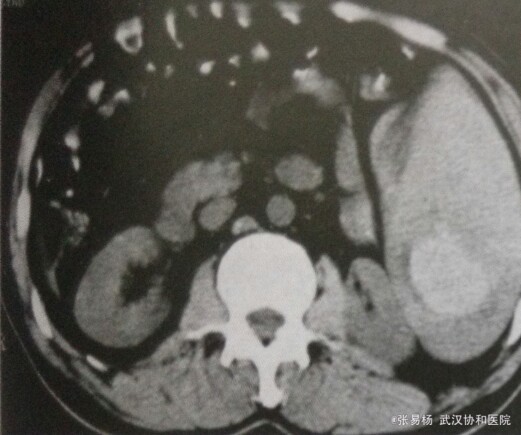

患者,男,65岁 主诉:左侧胸腹部疼痛2天 现病史:两天前从楼梯上摔落,后左侧胸腹部钝痛,今日加剧入院。

体检:胸廓挤压征+,左上腹压痛明显,脾区扣痛明显,无明显反跳痛,急诊腹部穿刺抽出不凝血。 辅检:CT示脾体积增大,脾实质内见结节状、斑片状高低混密度影,增强扫描脾血肿及包膜下积血无强化,脾实质强化。

行脾切除术,手术证实外伤性脾破裂出血、脾内血肿